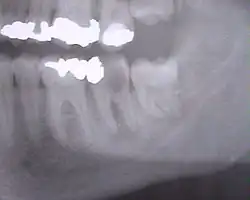

Lorsque la dent bute sur le collet de la deuxième molaire, elle est bloquée dans son extériorisation. On dit qu'elle est « enclavée ».

La dent est dite « incluse » lorsqu'elle est entièrement recouverte par l'os et la gencive, au niveau de la face postérieure de la racine de la deuxième molaire.

Entre 15 et 25 % des dents de sagesse mandibulaires sont incluses ou enclavées[13].

Les complications liées aux difficultés d'éruption des dents de sagesse sont les péricoronarites, phlegmons et cellulites, kystes péricoronaires, caries de la deuxième molaire, voire résorption de la racine de cette dernière. Ces complications sont rares (20 % des dents enclavées)[14]. Ce sont surtout les dents de sagesse mandibulaires qui créent ces pathologies, et une partie de ces problèmes sont d'origine de l'opercule, ou du lambeau de gencive qui, s'il existe, recouvre partiellement une dent de sagesse, surtout mandibulaire, et en dessous de lui débris alimentaires et bactéries peuvent causer la péricoronarite et la carie. L'opercule peut être enlevé dans une opération chirurgicale mineure, une operculatomie, et cela devrait empêcher les problèmes avec nettoyage.